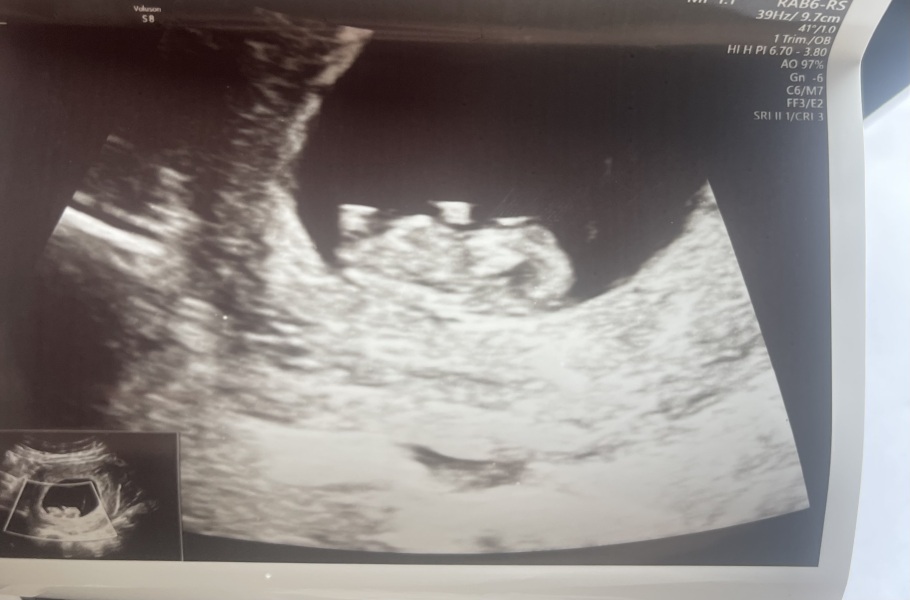

Reddy01 · 19/07/2024 07:52

Well this is different. My friend did early glimpse for me and got this!

I have my scan in a week but I thought the same as you lot so it'll be interesting. I'll keep you all posted!

Leg or nub?